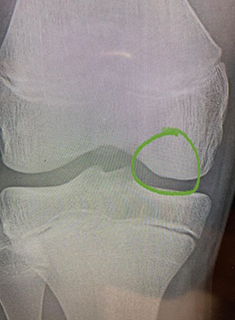

Surgical management is indicated when nonsurgical management fails, in unstable lesions, or when loose bodies are present. When surgery is done for these lesions the goal is maintain articular cartilage congruity, repair the defect, and fix unstable fragments. Figure 1 shows a young soccer athlete with an OCD lesion and Figure 2 shows the lesion healed 6 months after in situ fixation.

Figure 2